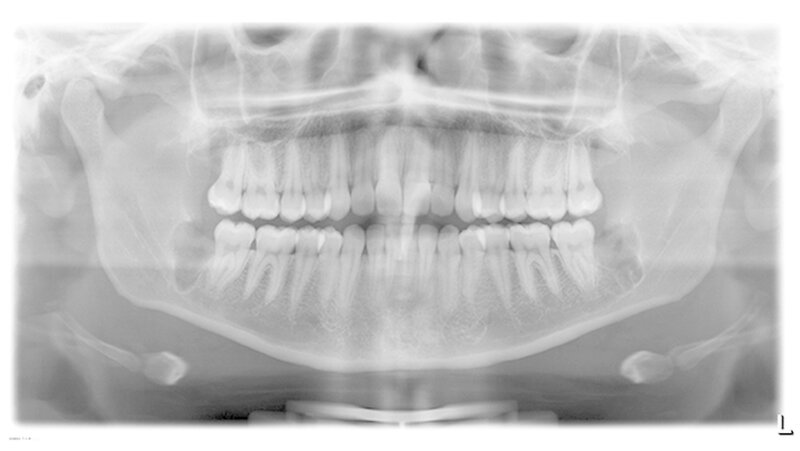

Aufgrund der engen Lagebeziehung der Weisheitszähne 38 und 48 zum Nervus alveolaris inferior (Abbildung 1) wurde zur weiterführenden Diagnostik eine digitale Volumentomografie (DVT) in der Praxis von Dr. Burkard Langenfeld in Friedrichshafen durchgeführt (Abbildungen 2 und 3).

Somit konnte auf eine Verplattung mittels Osteosynthese-Material verzichtet werden. In alle Extraktions-Alveolen wurde Gelatamp, Firma Roeko, eingebracht. Der Nahtverschluss erfolgte atraumatisch mit Vicryl 3/0, Firma Ethicon. Zur Dokumentation wurde postoperativ ein digitales OPG angefertigt.